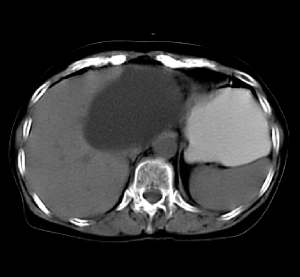

患者无任何不适及阳性体征,超声体检时发现,未做增强扫描。囊影密度均匀,ct值略高于水,囊影壁薄光滑,囊内密度均一。定性诊断不难,应是个囊肿。请大家做个定位诊断

病灶上部层面与肝脏交界清楚但不太截然,下部层面与肝之间可见线状高密度带,考虑由囊块压迫肝实质形成,考虑caroli氏病,其次考虑左肝囊肿向下向肝外生长,另外其他来源囊肿及消化道重复畸形不排除